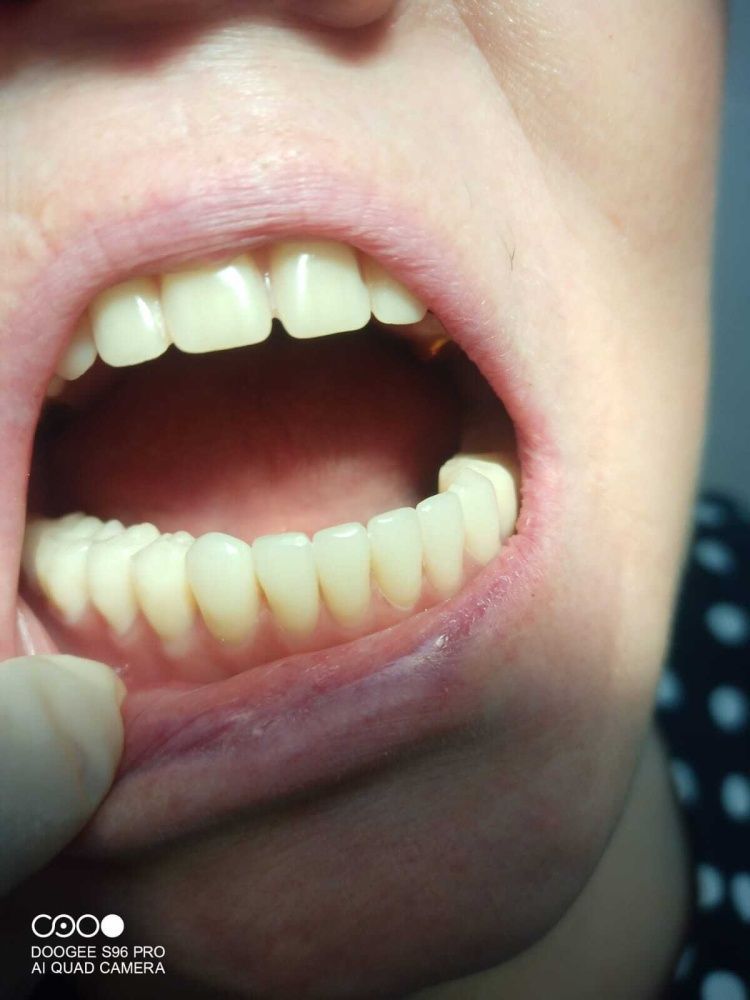

К нам в клинику, к доктору Шаймарданову Ф.Т., обратилась пациентка И. с жалобами на полное отсутствие зубов в нижней челюсти и невозможность ношения полного съемного пластинчатого протеза, так как он не фиксируется на нижней челюсти. Врач предложил установить 4 имплантата в нижнюю челюсть с дальнейшим протезированием балочной системы условно съемного пластинчатого протеза с опорой на имплантаты. Такой протез хорошо фиксируется на имплантатах и обеспечивает удобные условия для гигиены полости рта и протеза.